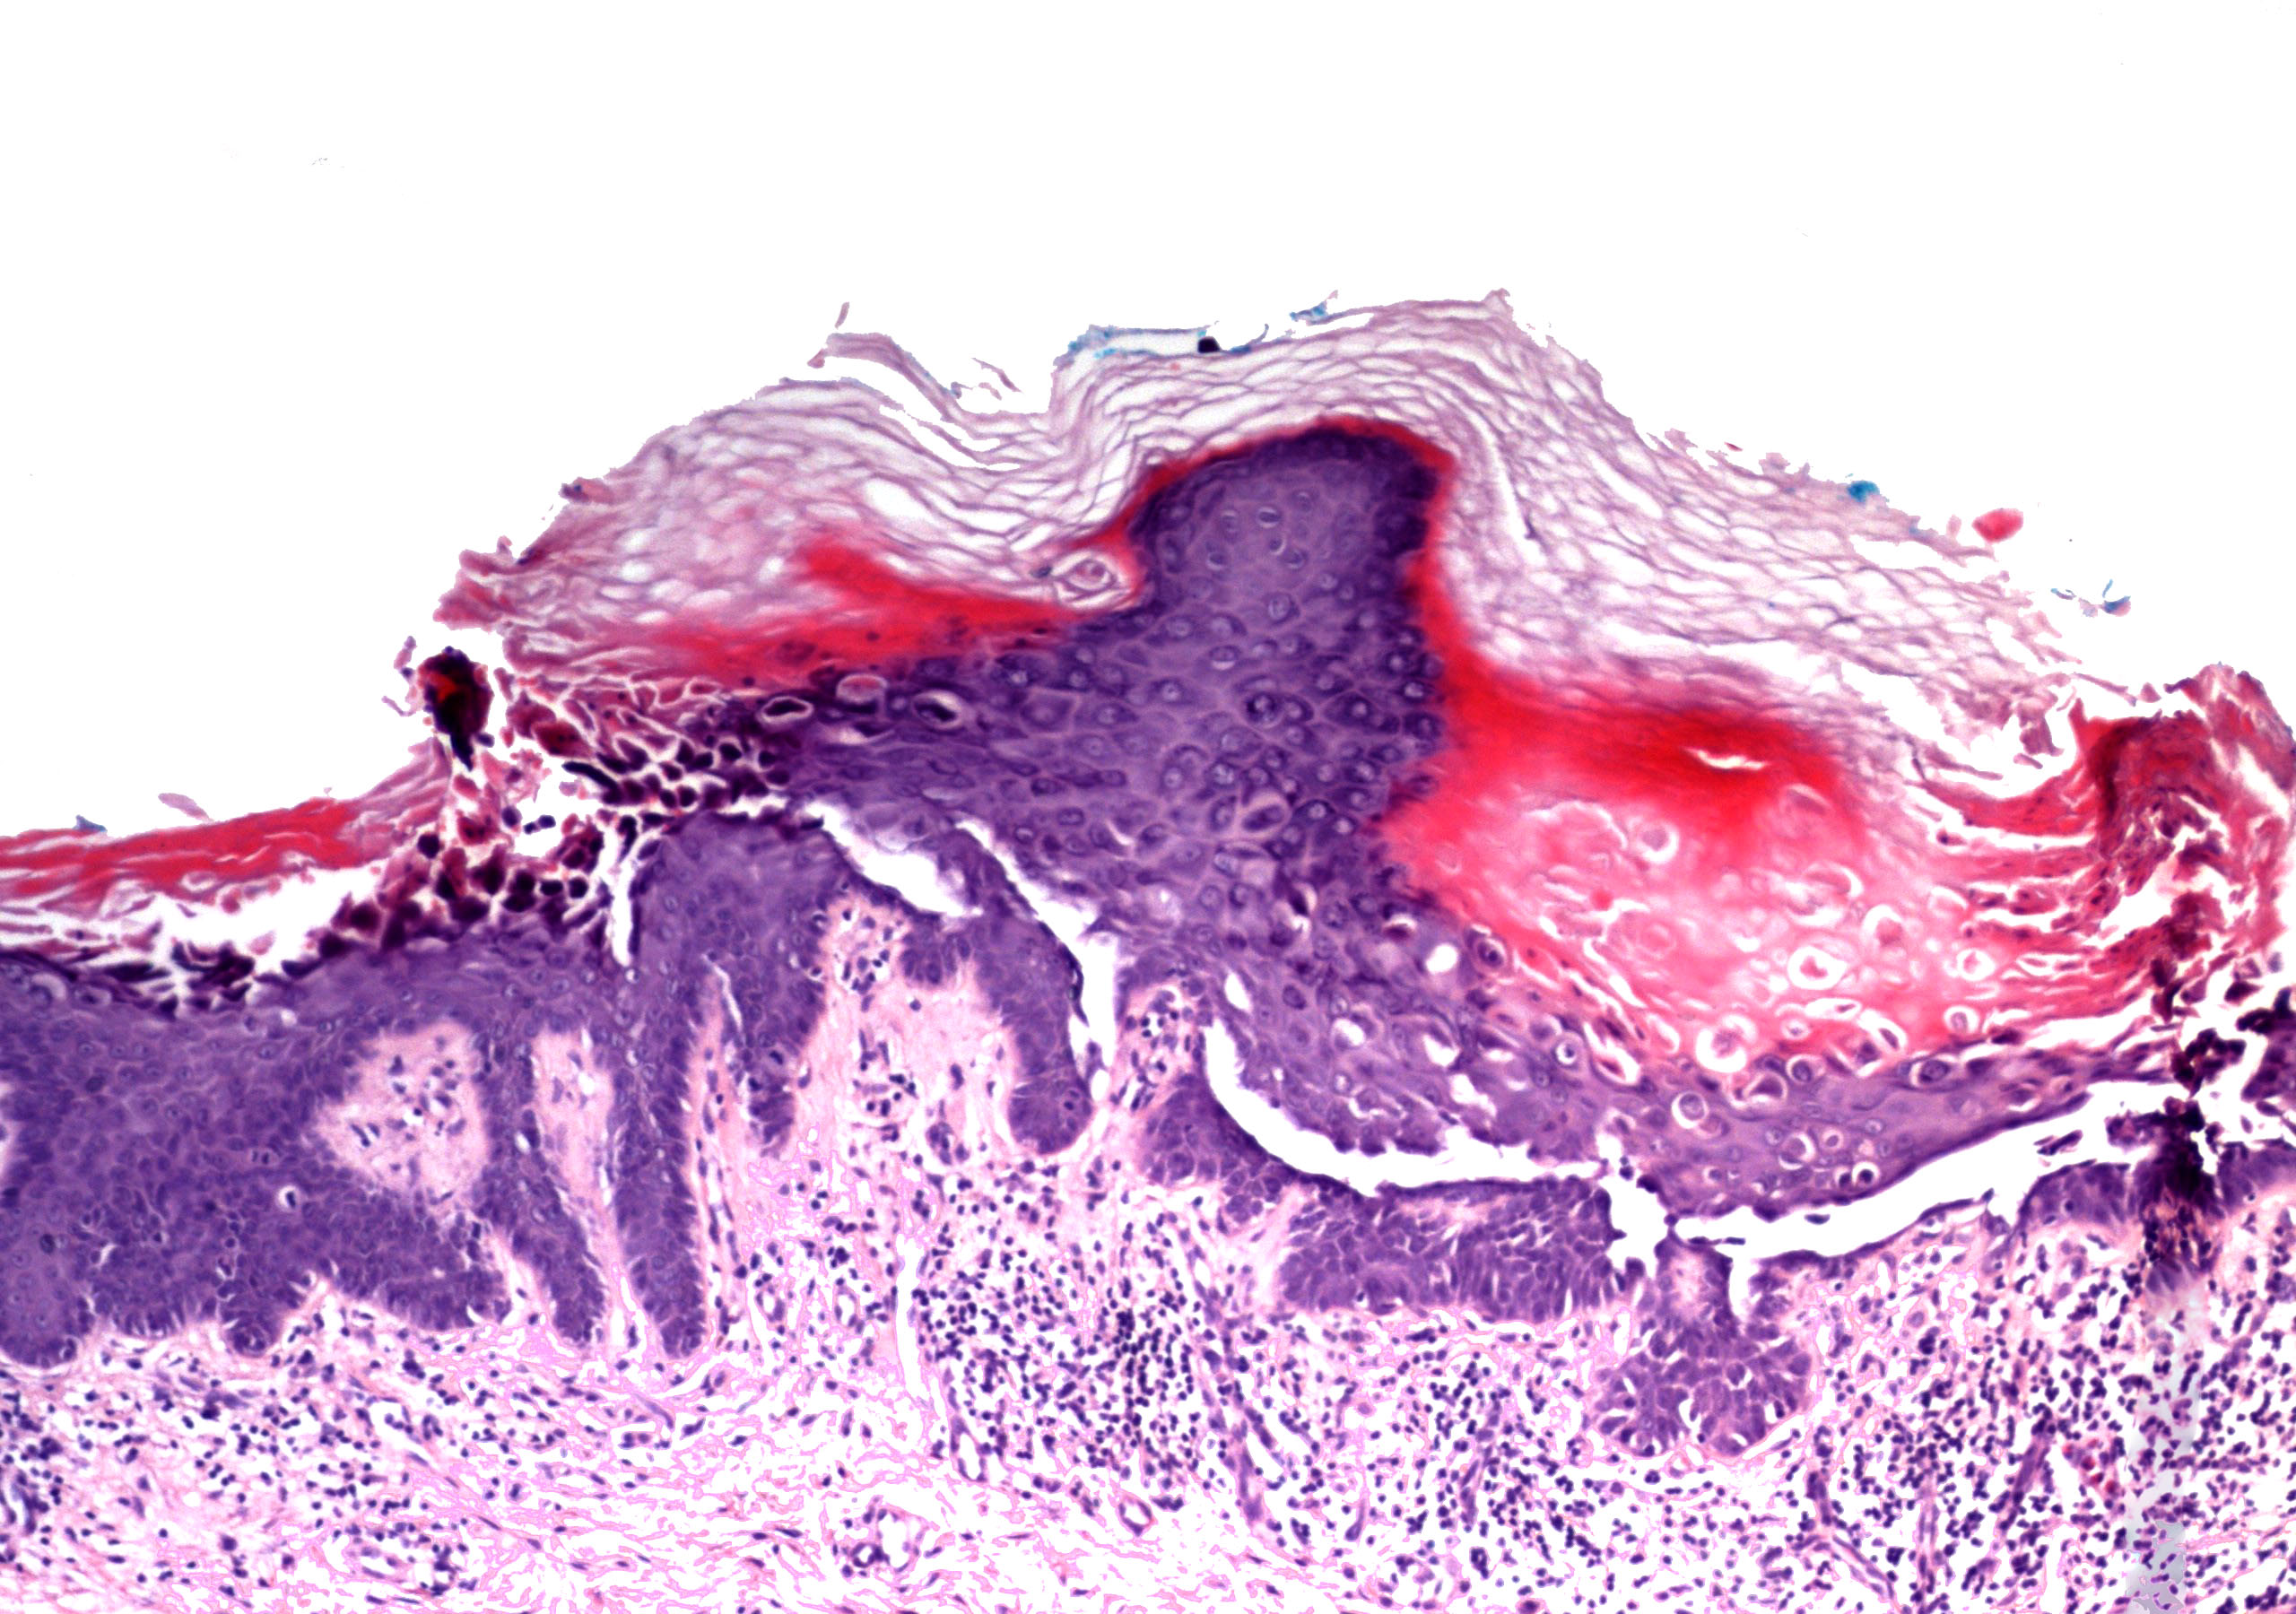

Microscopic (histologic) description

- Parakeratosis

- Variable epidermal thickness

- Acantholysis with characteristic dyskeratosis forming corp ronds and grains

- Corp rond: rounded keratinocyte in superficial spiny and granular layer with basophilic / pyknotic nucleus, perinuclear halo and often a rim of eosinophilic cytoplasm (J Dermatol 2017;44:232)

- Grain: elongated keratinocyte in the stratum corneum with small basophilic nuclei and intensely pink cytoplasm; appears as plump parakeratosis; may form tiers (J Dermatol 2017;44:232)

- Corp rond and grain type dyskeratosis is classical but not specific for Darier disease (see Differential diagnosis)

- Suprabasal acantholysis and clefting with retained single layer of basal keratinocytes overlying dermal papillae which appear to project into the acantholytic cavity (villi) (J Dermatol 2016;43:275)

- Frank bullae may occur in cases with extensive acantholysis and large clefts (Arch Dermatol 1982;118:278)

- Superimposed fungal, bacterial and herpetic infections may be seen (J Eur Acad Dermatol Venereol 2013;27:1405, Am J Dermatopathol 2017;39:370, Dermatol Ther 2020;33:e14500, Br J Dermatol 2015;172:837, Acta Derm Venereol 2017;97:139)

- Variable mild perivascular inflammatory cell infiltrate

- Variants: extensive pseudoepitheliomatous hyperplasia, comedonal lesions with prominent villus formation and hemorrhagic bullous lesions (Am J Dermatopathol 2015;37:323, J Dermatol 2006;33:477, J Cutan Med Surg 2016;20:478)

Microscopic (histologic) images